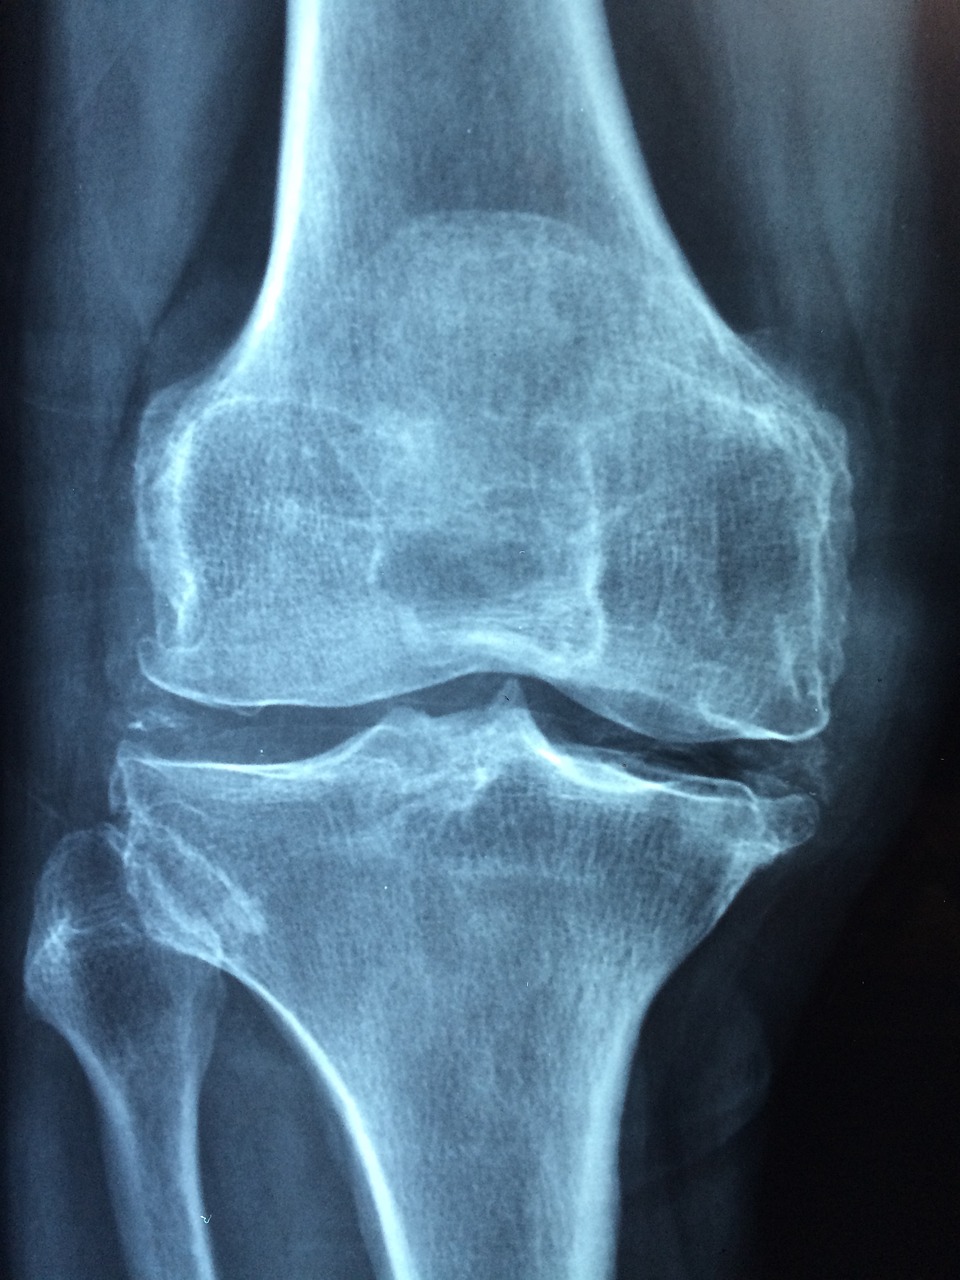

무릎 엑스레이 사진